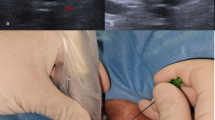

The VasoStat hemostasis device (Forge Medical Inc., Bethlehem, PA), recently introduced in the United States and Japan, was developed to address several limitations of existing hemostasis devices by utilizing more focused (≤ 2 cm2 area of compression) and mechanically graded compression of the artery to achieve hemostasis (Fig. 1). The VasoStat device is FDA-cleared and CE-marked for hemostasis after both upper extremity and transpedal access, and its focused compression mechanism may lead to more rapid hemostasis compared to larger compression surfaces by band devices such as the TR Band [24,25,26]. This study investigated the use of the focused compression device following upper and lower extremity arterial access and assessed patient and operative variables influencing times to hemostasis.

VasoStat Hemostasis Device. A central convex compression surface provides graded puncture site compression using a ratcheting mechanism incorporated within the base of the device. An overlying elastomeric adhesive pad further maintains alignment over the arterial access site. (A/B Isometric and front views of device, C radial, D distal radial, E combined posterior tibialis and dorsalis pedis)